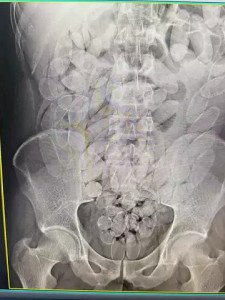

Grupo formado por oito bolivianos, sendo uma mulher e sete homens, foi flagrado transportando 645 cápsular de cocaína no estômago durante fiscalização da Receita Federal no posto Esdras, em Corumbá.

Os raios X confirmaram que os oito haviam engolido cápsulas de pasta base de cocaína. O material foi retirado de forma segura por equipe médica, totalizando 645 cápsulas. Após o procedimento, todos foram encaminhados à PF (Polícia Federal), onde permanecem à disposição da Justiça.